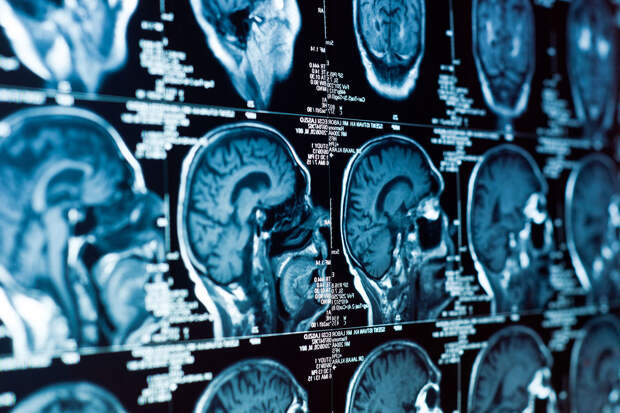

Глиобластома отличается быстрым ростом и высокой склонностью к рецидивам.

Чаще всего этот тип злокачественной опухоли локализуется в височной и лобной частях головного мозга. Стандартное лечение включает хирургическое вмешательство, лучевую терапию и/или химиотерапию темозоломидом. Однако эти методы лечения не отличаются высокой эффективностью и оказывают побочные эффекты.Ученые поставили перед собой задачу найти способ борьбы с глиобластомой, который воздействует на раковые клетки и обучает иммунную систему распознавать их самостоятельно.